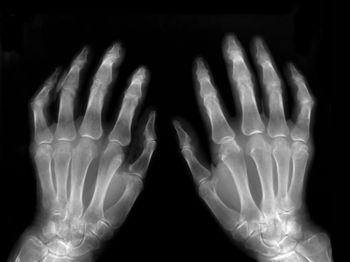

Parenteral methotrexate therapy is more successful than oral methotrexate in achieving optimal disease activity control in rheumatoid arthritis, with no increased adverse effects, say researchers writing in PLoS One this month.

Fluorescence optical imaging, which enables visualization of inflammation in the hands in rheumatic joint diseases, correlates with ultrasound as a validated and well-established imaging technique in daily rheumatological practice, say researchers writing in Arthritis Research & Therapy this month.

In patients with rheumatoid arthritis, methotrexate adherence is suboptimal and associated with certain demographics, medication experience, and beliefs about medicines, say researchers writing in ACR Open Rheumatology this month.

Triple therapy and methotrexate‐based biologic disease‐modifying antirheumatic drug (DMARD) combinations were superior to methotrexate alone for both American College of Rheumatology (ACR50) response and remission in patients with rheumatoid arthritis, say researchers writing in Arthritis Research & Therapy last month.